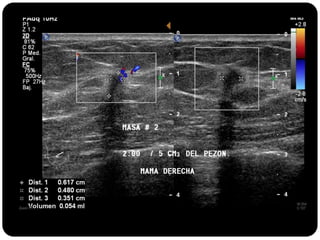

Paciente femenina de 66 años con historia clínica de 1er gesta antes de los 30 años y antecedentes de lactancia positiva, presenta una lesión palpable en la mama derecha. Los estudios radiológicos indican un diagnóstico de bi-rads 5, con biopsias revelando adenocarcinoma lobulillar infiltrante en la glándula mamaria derecha y adenocarcinoma ductal in situ en la izquierda. El caso fue evaluado por las doctoras Jacqueline Preciado Vargas y Beatriz E. González Ulloa.